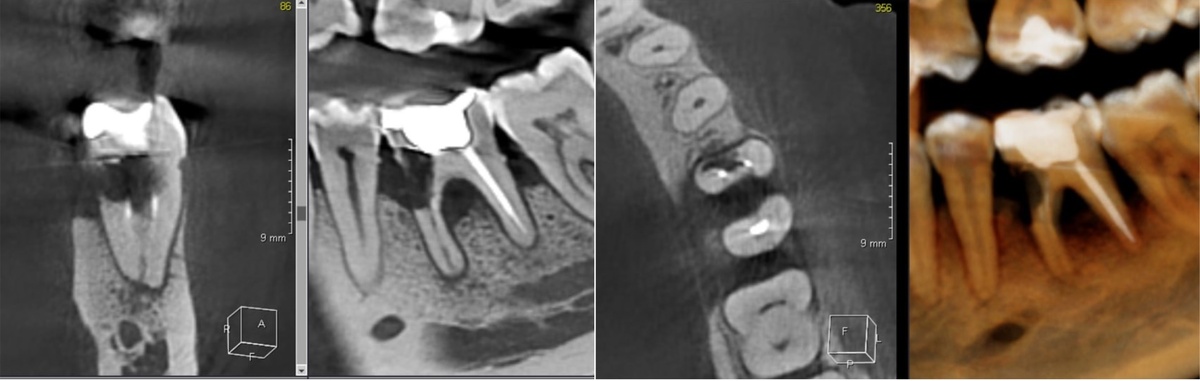

Периодонтит и резорбция

Периодонтит и резорбция корня часто сопутствуют друг другу, представляя собой комбинацию воспаления и патологического рассасывания твердых тканей зуба.

На осмотре:

• может быть незначительная чувствительность или ее отсутствие

• десна может выглядеть спокойно

На КЛКТ:

• виден очаг воспаления у верхушки корня

• определяется степень разрушения костной ткани

• выявляется сопутствующая резорбция

Чем это опасно: без точной диагностики воспаление может перейти в хроническую форму и привести к значительной потере костной ткани, а прогрессирующая резорбция тканей зуба значительно осложнит лечение или приведет к смене тактики вмешательства.